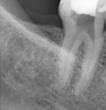

→ 2 lengths: 21 and 25 mm

In the past years the heat-treated Ni-Ti rotary files have become a gold standard in endodontics. However, heat-treated nickel-titanium endodontic instruments produced with the electro discharged machining are on a completely another level offering some unparalleled properties. Scientific studies show surprisingly high values of cyclic fatigue resistance, increased cutting efficiency and increased wear resistance with low degradation. The HyFlex EDM files systems offer the user a simple, predictable, safe, and cost-effective instrumentation in all clinical types of root canals, form straight to severely curved. The new OGSF sequence makes it possible to enlarge the root canal in a minimally invasive way to 30/0.04, making the EDM system even more versatile. If needed the root canals can be enlarged with EDM Hyflex 40/0.04, and further with the reducing taper from 50/0.03 to the file size up to 60/0.02 without loosing on the flexibility of the files to best preserve the original shape of the root canal all the way to the apex. Pre-bending the controlled memory EDM files also offers a simple management for by-passing ledges previously formed in the root canal. The HyFlex EDM system is the system of choice for beginners and advanced users.

Dr. Tomaž Hitij

A versatile file system can adapt to many clinical scenarios and increase instrumentation predictability. The new HyFlex EDM OGSF sequence has just arrived to make everyday endodontic challenges delightful to treat. Lovely conservative OGSF shapes and ease of use.

With COLTENE’s new HyFlex EDM OGSF sequence endodontic procedures becomes easier. Owing to the defined, easy-to-remember sequence, learning to use these files is relatively quick, and being intuitive, the sequence is easily recalled and repeated.